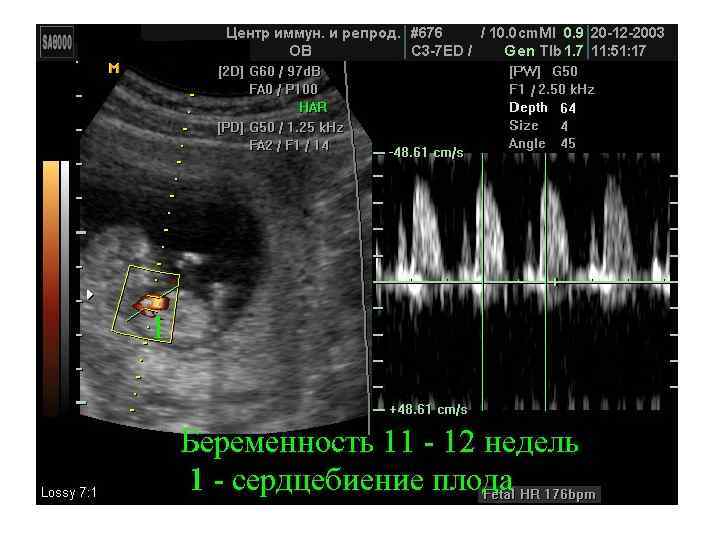

Скрининговое ультразвуковое обследование беременных Приказу Минздрава РФ № 457 от 28 декабря 2000 г. • 10 -14 недели беременности • 20 -24 недели беременности • 32 -34 недели беременности

Скрининговое ультразвуковое обследование беременных Приказу Минздрава РФ № 457 от 28 декабря 2000 г. • 10 -14 недели беременности • 20 -24 недели беременности • 32 -34 недели беременности

Определение сроков беременности при УЗИ (!? ) • Результат УЗИ полученный • в первом триместре (первые 12 недель беременности) позволяет вычислить срок родов с точностью 1 -3 дня, • во втором триместре (от 13 до 28 недель) ошибка увеличивается до 7 дней, • а после 28 недель (III триместр) очень сложно судить о сроке беременности по ультразвуковому размеру малыша.

Определение сроков беременности при УЗИ (!? ) • Результат УЗИ полученный • в первом триместре (первые 12 недель беременности) позволяет вычислить срок родов с точностью 1 -3 дня, • во втором триместре (от 13 до 28 недель) ошибка увеличивается до 7 дней, • а после 28 недель (III триместр) очень сложно судить о сроке беременности по ультразвуковому размеру малыша.

Определение сроков беременности при УЗИ (!? ) • Нарастание УЗ-ошибки в вычислении срока родов связано с тем, что о сроке беременности при этом исследовании судят по размеру ребенка. • Уже известно, что основные массо-ростовые отличия возникают у малышей в последнем триместре беременности (вес при рождении может составлять от 2500 до 4500 г), а до этого срока размеры ребенка довольно точно соответствуют определенному сроку беременности и не слишком отличаются у разных деток.

Определение сроков беременности при УЗИ (!? ) • Нарастание УЗ-ошибки в вычислении срока родов связано с тем, что о сроке беременности при этом исследовании судят по размеру ребенка. • Уже известно, что основные массо-ростовые отличия возникают у малышей в последнем триместре беременности (вес при рождении может составлять от 2500 до 4500 г), а до этого срока размеры ребенка довольно точно соответствуют определенному сроку беременности и не слишком отличаются у разных деток.